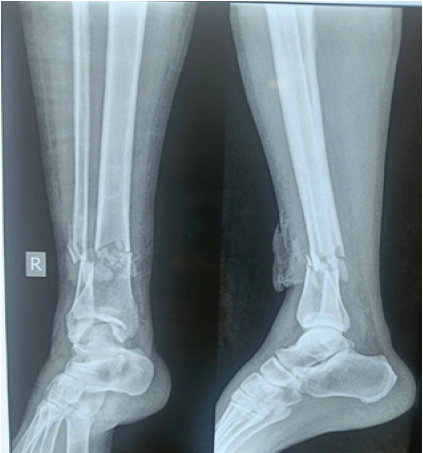

A 65-year-old male patient met with a road traffic accident and sustained a Gustilo Anderson Type-3A fracture of tibia with bone exposed. On radiology, it is of AO 42A3 fracture, that is, extra-articular distal tibial fracture with metaphyseal comminution (Fig. 1). He was treated at a different center initially with debridement and primary fixation with anteromedial fixation with distal tibial LCP and fibula is fixed with a one-third tubular plate (Fig. 2).

Figure 1: X-ray after initial trauma.